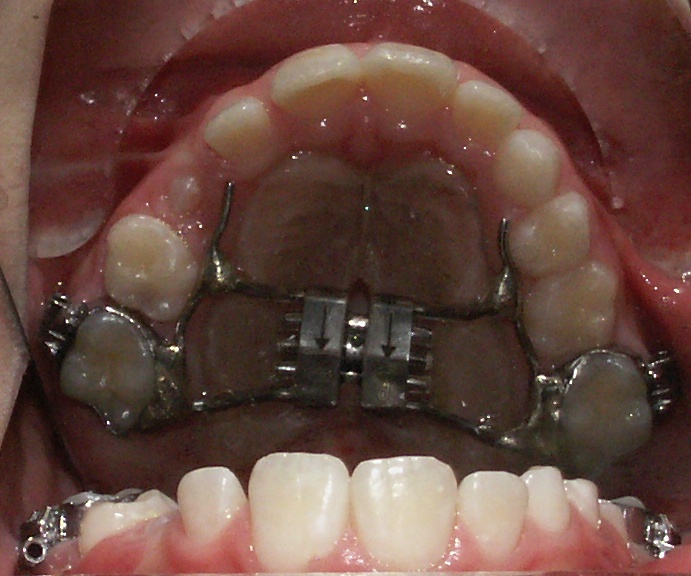

Per risolvere il problema, è comune impiegare l’espansore palatale (link al sito-pagina apparecchio): un dispositivo ortopedico molto utilizzato in ortodonzia. È un apparecchio fisso, viene cementato sui secondi molaretti da latte o sui primi molari permanenti, con una vite centrale che deve essere attivata quotidianamente per un periodo stabilito dallo specialista.

Allargare il palato richiede forze lente e costanti. L’efficienza dell’apparecchio si manifesta con la comparsa di un piccolo spazio tra gli incisivi centrali superiori. Solitamente questo particolare desta molta preoccupazione tra i genitori ma, in realtà, fa assolutamente parte della terapia e andrà successivamente incontro a chiusura nel giro di un mese.

L’attivazione consiste nel far svolgere alla vite 1/4 di giro tramite l’uso di un’apposita chiavetta. In questo modo, ogni 1/4 di giro svilupperà un’espansione di 0,24 mm e l’apaprecchio si manterrà costantemente attivo, dando vita alle forze lente e costanti prima citate.

Per compiere un’attivazione basterà agganciare una chiavetta all’interno della vite, seguire il senso della freccia compiendo 1/4 di giro.

La freccia, che punta sempre verso il palato molle, quindi si dirigerà sempre posteriormente.